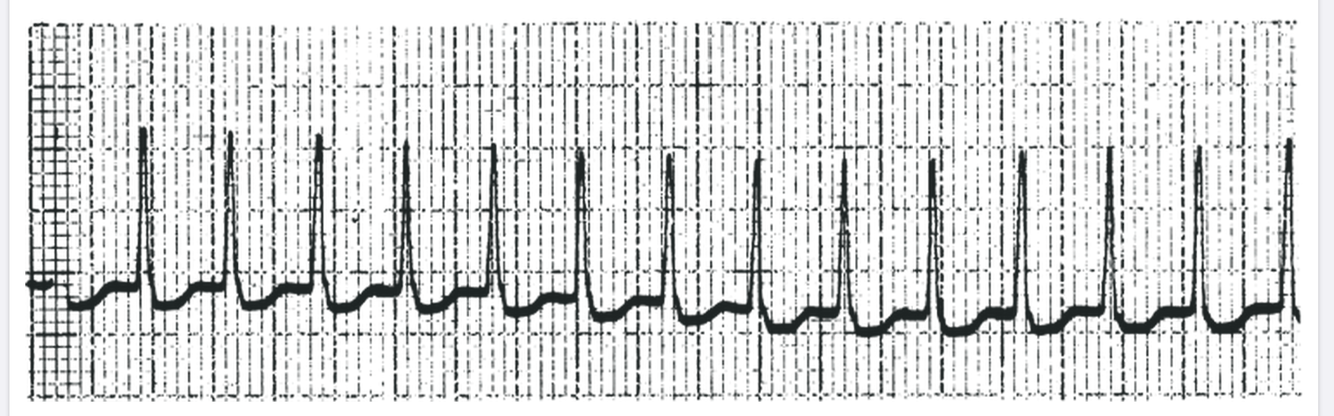

What is this?

3rd Degree AV Block

P waves march on

QRS are widened - they originate from within distal ventricular system, not bundle of His